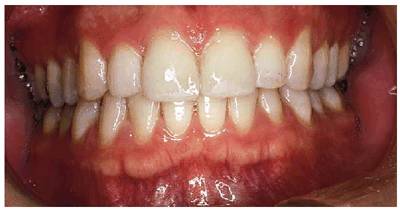

patient (Figures 17-1A to

C

Figure 17-1A to C: These photographs illustrate the complex dental condition of a 71-year-old male: (A) The palatal cervical regions of the maxillary anterior teeth exhibit sharp, wedge-like lesions that are characteristic of abfraction. These areas would be difficult, if not impossible, to have resulted from toothbrush abrasion. (B) The buccal aspects of the maxillary posterior teeth show smooth, concave configurations that are consistent with toothbrush abrasion and/or erosion. (C) The buccal surfaces of the mandibular teeth have lesions that possess components of both abfraction (sharp margins in the occlusal regions) and abrasion (concave geometry and gingival recession in the cervical regions).